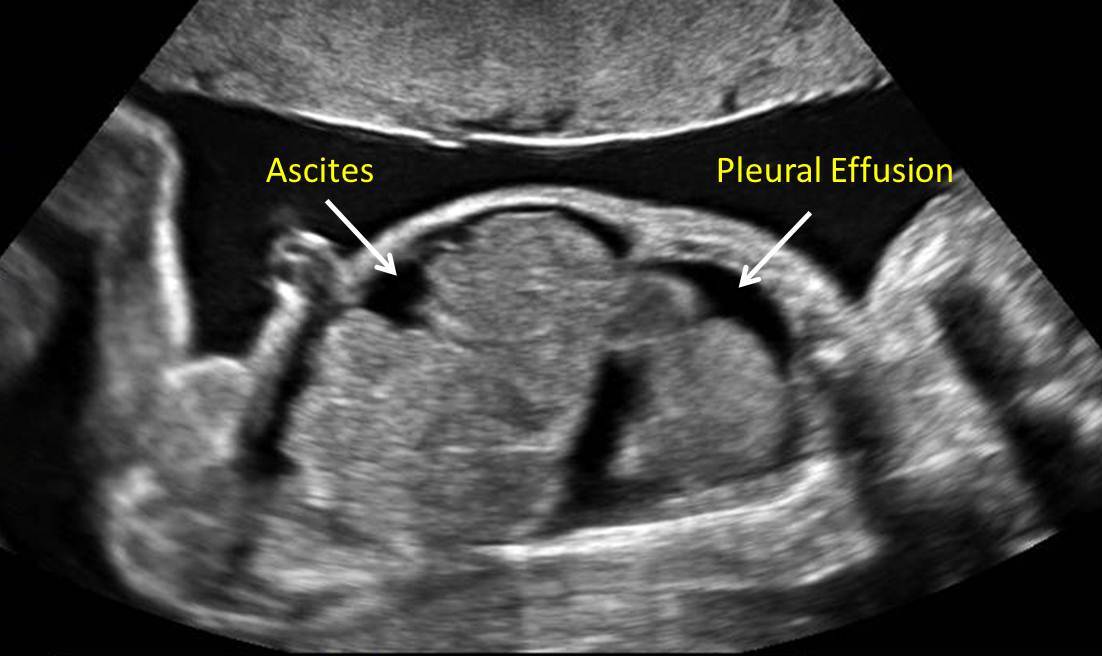

تأثیر استرس بر سیستم قلبی-عروقی جنین مانند یک زنجیره واکنش است که از مادر شروع میشود و به جنین میرسد. استرس مزمن میتواند جریان خون جفتی را مختل کند و اکسیژنرسانی به جنین را کاهش دهد، که این موضوع بر رشد قلب تأثیر مستقیم دارد. بر اساس یافتههای "Controlling fetal stress for preventing adverse health conditions in neonates and children"، استرس مادر میتواند منجر به هیپوکسی جنینی شود، که در آن قلب جنین برای سازگاری با کمبود اکسیژن، تغییرات ساختاری ایجاد میکند.

برای نمونه، در مواردی که مادران تحت استرس شدید قرار دارند، جنین ممکن است با افزایش فشار خون ریوی مواجه شود، که این میتواند زمینهساز مشکلات قلبی در آینده باشد. آمارها نشان میدهد که حدود ۱۰ تا ۱۵ درصد نوزادان متولدشده از مادران استرسزده، خطر بیشتری برای نقصهای قلبی دارند.